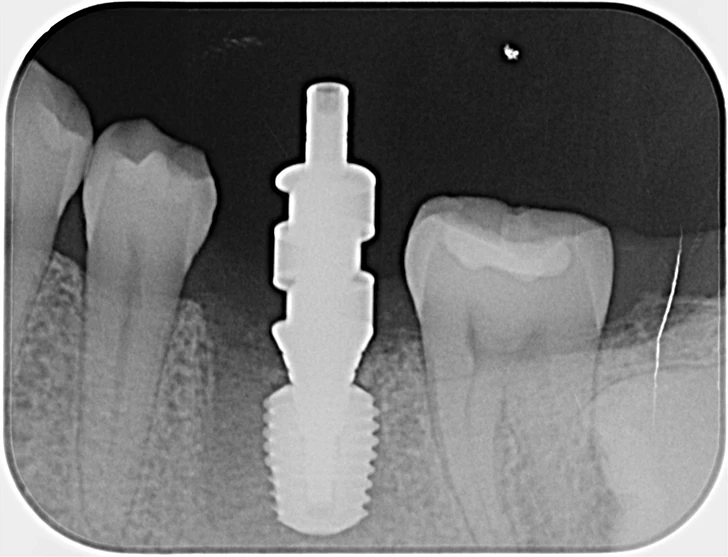

40代、女性、左下噛むと痛いこと主訴に来院され、インプラント治療を行いました。

| 診断結果 | 左下6番歯根破折 |

| 治療内容 | 抜歯即時インプラント |

| 治療期間 | 8週間 |